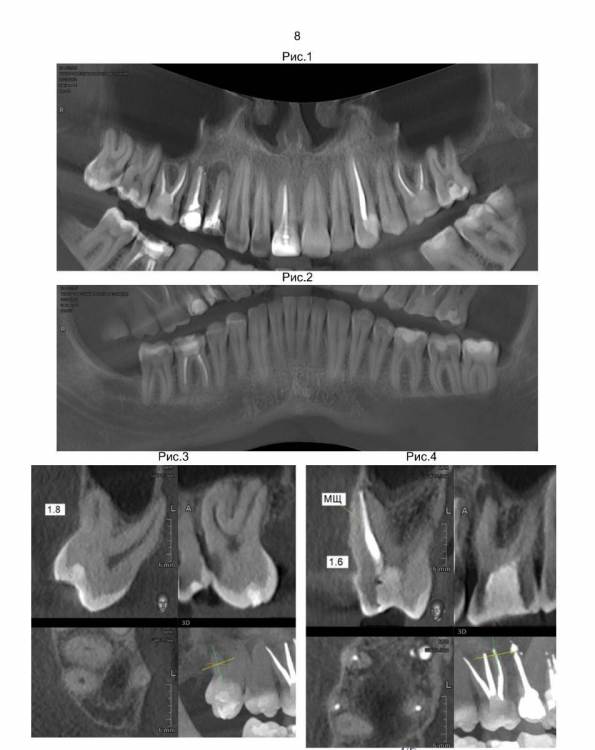

Здравствуйте. Сделал КТ всей челюсти с описание врача рентгенолога.

Врач стоматолог написал планы лечения. Больше всего меня смущает удаление трех верхних зубов 1.4, 1.5, 1.6 т.к. на концах корней у этих зубов развиваются опухоли, и установка на их место имплантов сразу после удаления. Правильно ли это? Просто до этого слышал, что перед установкой импланта требуется около трех месяц на заживление. Стоматолог говорит, что надо сразу установить импланты, что бы избежать деформацию десны. Потом через примерно три месяца на эти три импланта будут ставиться коронки.

И по третьему плану лечения зубы 1.8 и 3.8 просто удаляются.